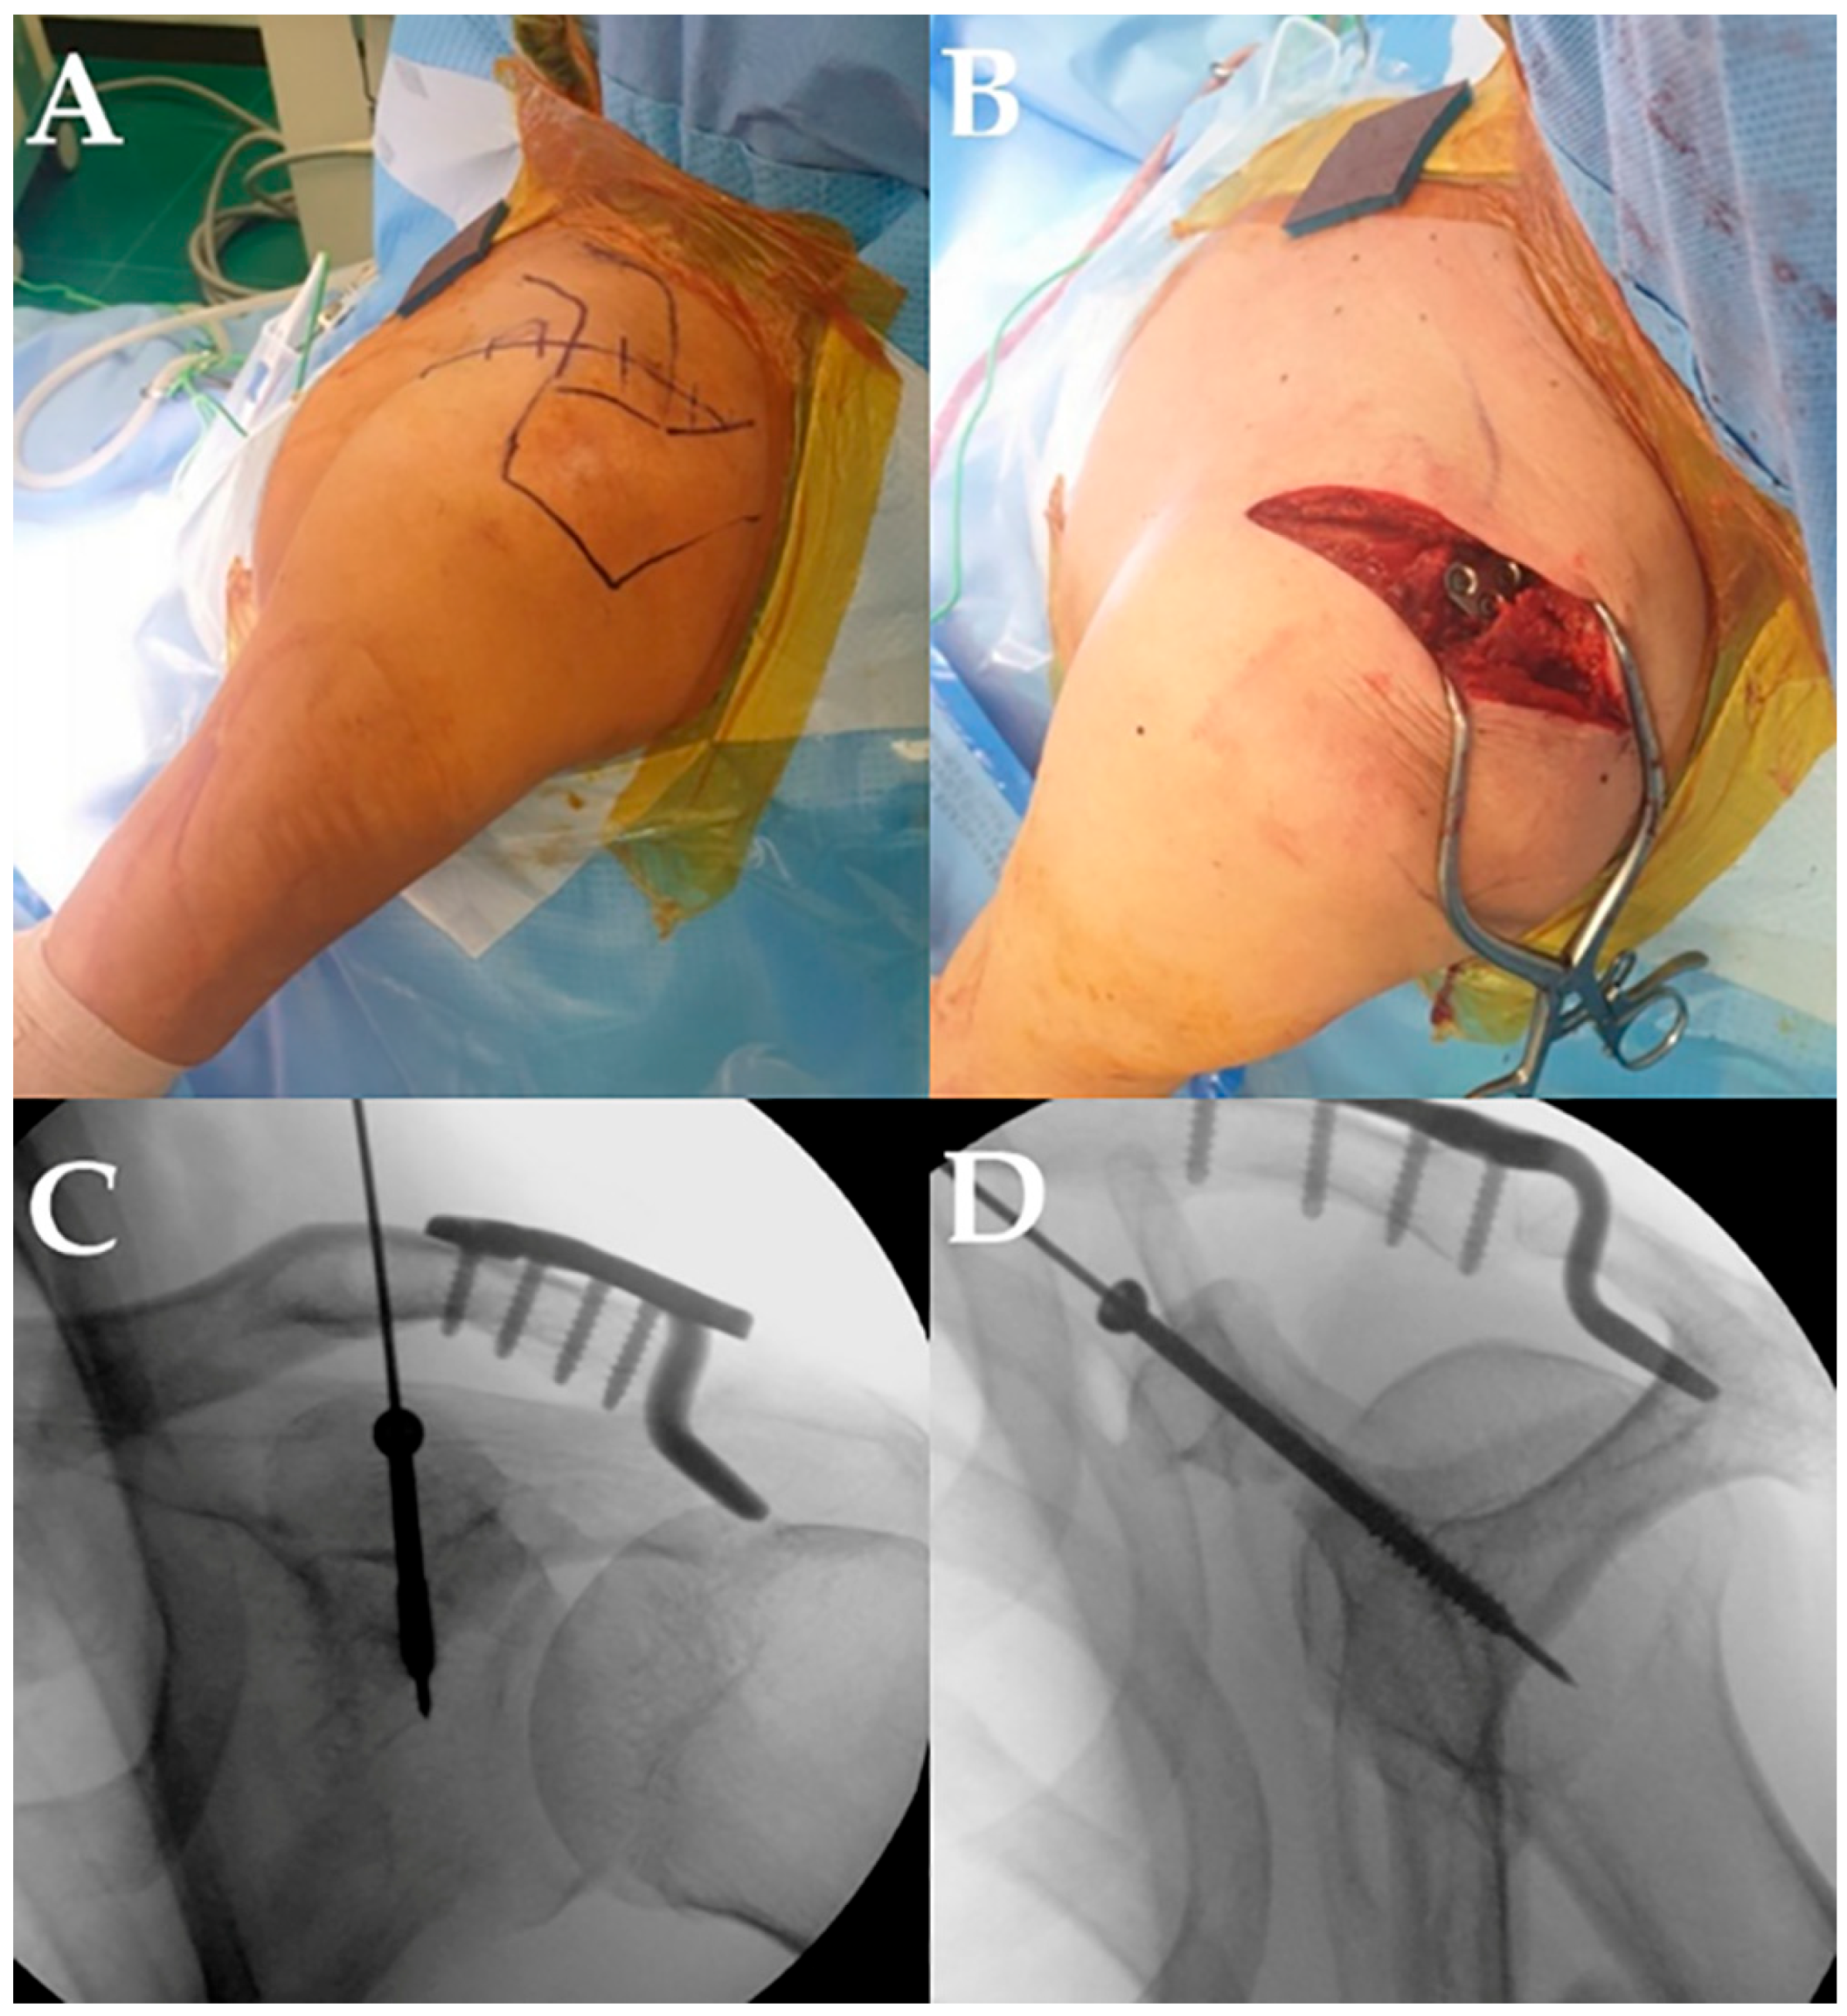

2.2. Surgical Technique and Rehabilitation